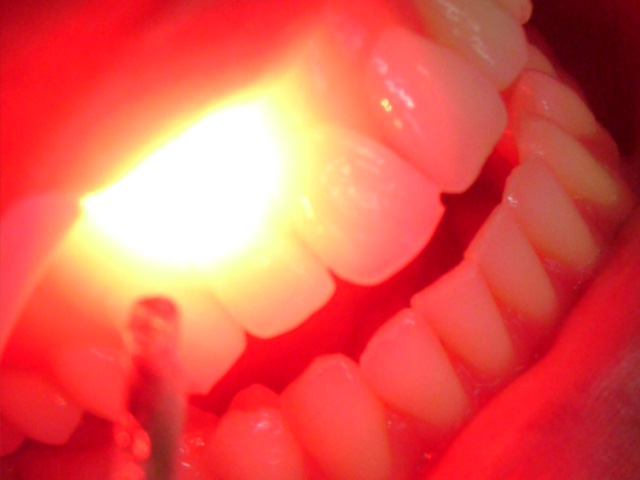

«El 22 de octubre en el hospital Bollini de La Plata vino una eminencia a dar una charla sobre el uso del láser en odontología y salud, hace 10 años que se esta usando y cada vez son mas los usos que se dan en la salud. Recién ahora esta llegando a los odontólogos de nuestro pais».

Por otra parte, Giralt explicó «Hay tres tipos de láser, uno para trabajar la cuestión terapéutica y uno de alta potencia que sirve para realizar cirugías, y uno de súper alta potencia que seria el que reemplazaría al torno. El valor de este láser terapéutico es aproximadamente de 1.500 dolares, y es un precio que las clínicas lo podrían costear. Pero muchas veces, por falta de conocimiento, no se realizan este tipo de inversiones. »